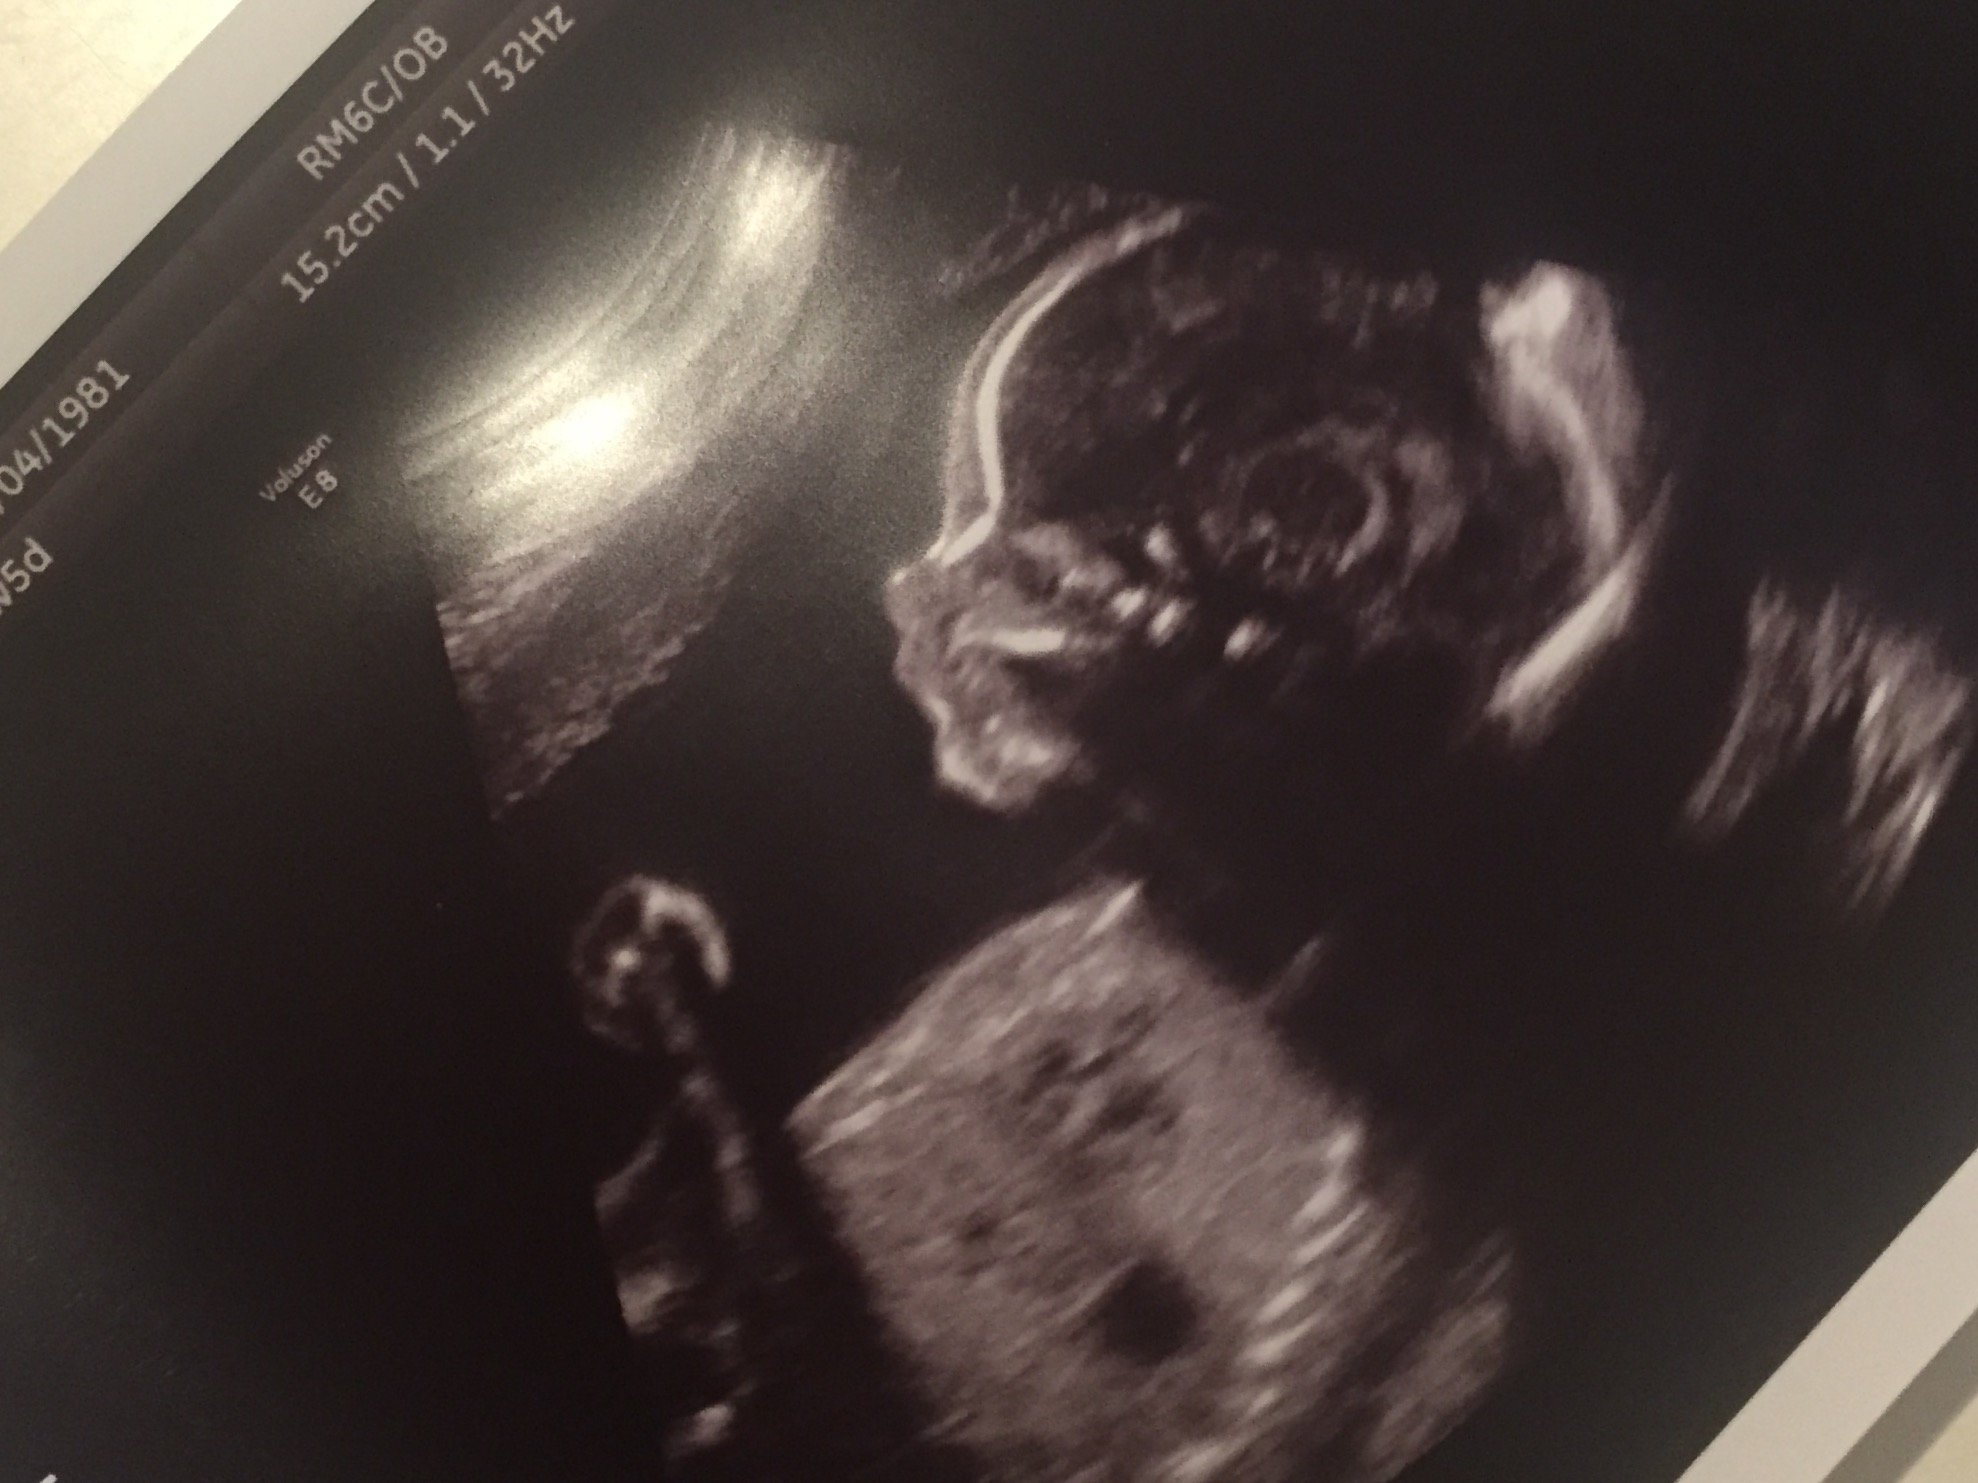

• @Drove2u - glad the scan went well. I just love when you can see all of their features in the profile.. like that little nose is too cute!